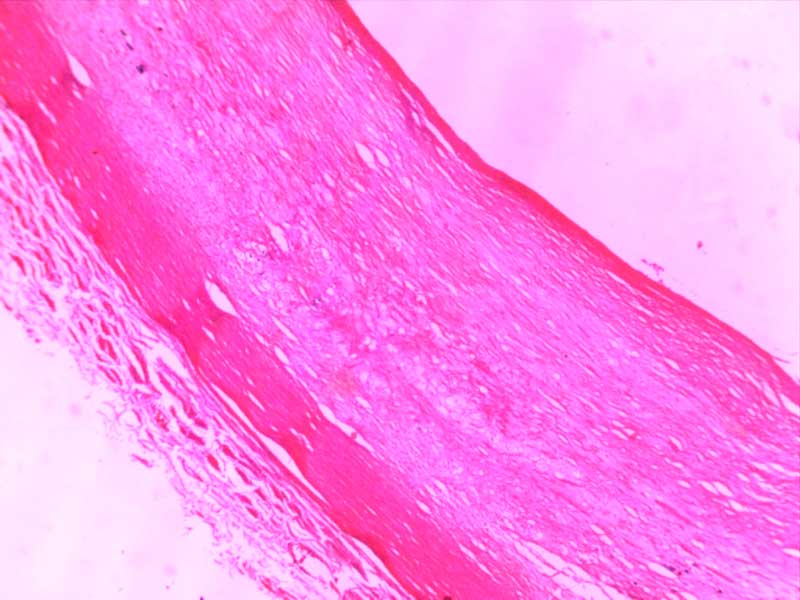

主动脉粥样硬化-4倍